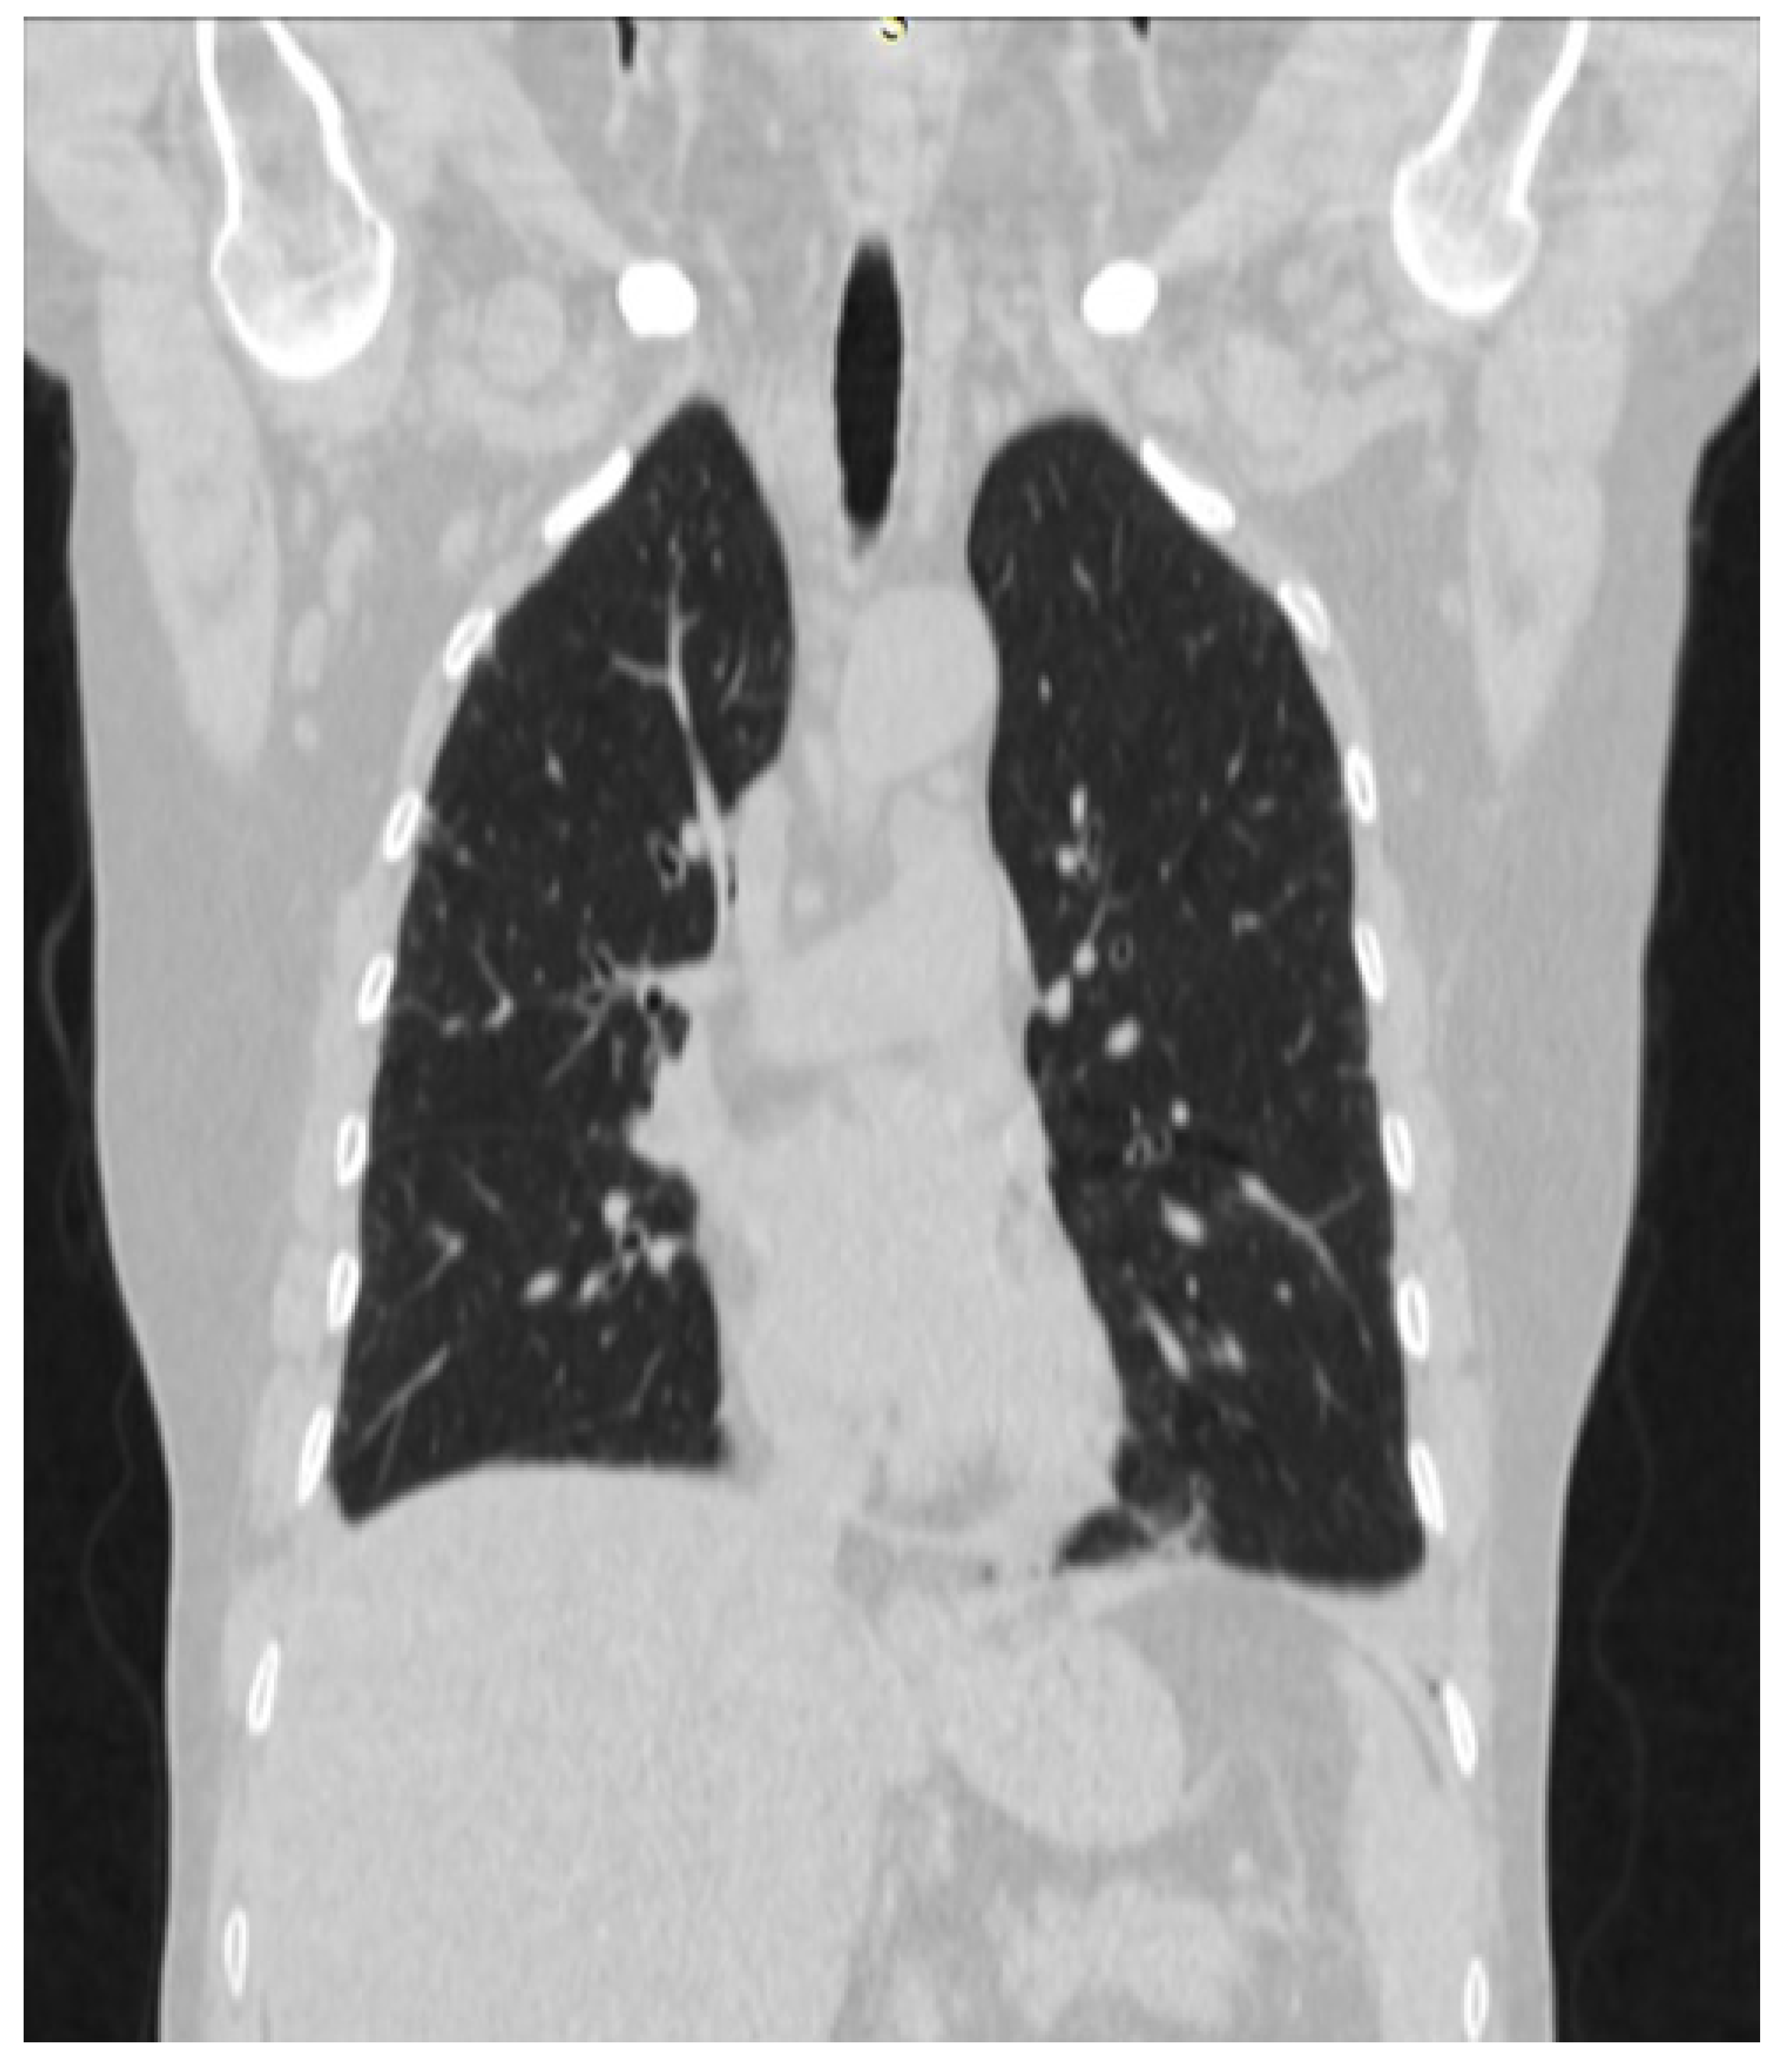

2. Case Presentation

4.2. Early Pulmonary Involvement in Antisynthetase Syndrome—Diagnostic and Prognostic Value